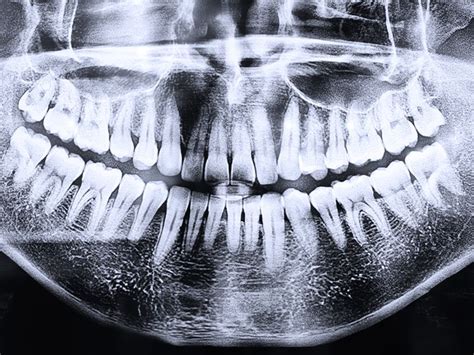

Nuestra labor es que tu primer contacto con nosotros sea agradable y sobre todo familiar, eliminando los posibles nervios iniciales y ayudándote a resolver todas tus dudas. El segundo paso a seguir, es hacerte una radiografía panorámica para dar un mejor diagnóstico. Después de realizarte la radiografía panorámica nuestros especialistas te harán una exploración minuciosa del estado de tu salud bucodental y poder proponer el mejor plan de tratamiento a tus necesidades. En clínica dental de urgencias, los pacientes reciben una atención integral de un dentista experimentado y un personal bien entrenado.